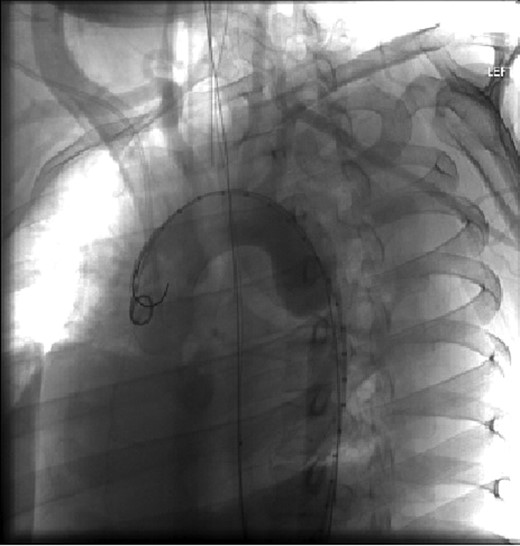

Chest, pelvis and right lower extremity X-rays were obtained. Chest X-ray findings are shown in Fig. 1. Pelvic X-ray was negative for acute injuries. Right lower extremity X-ray revealed the presence of a right tibia-fibula fracture and the right lower extremity was immobilized with a posterior splint.

Aortic arch and descending thoracic aorta visualized by CTA with contrast pre-placement of stent.